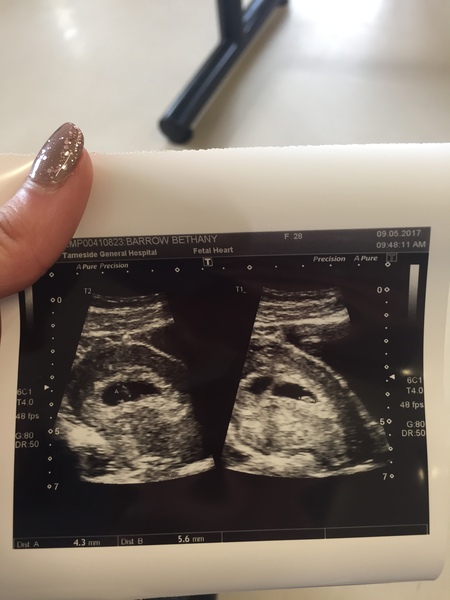

Bethany891 · 11/05/2017 06:56

Ours are fraternal twins and no history off twins I'm the first ! 😲 Excited and scared at the same time . Good luck on your rescan do you have a history off twins ? Congratulations !!

Bethany891 · 11/05/2017 06:58

6 week scan

December 2017 #4!